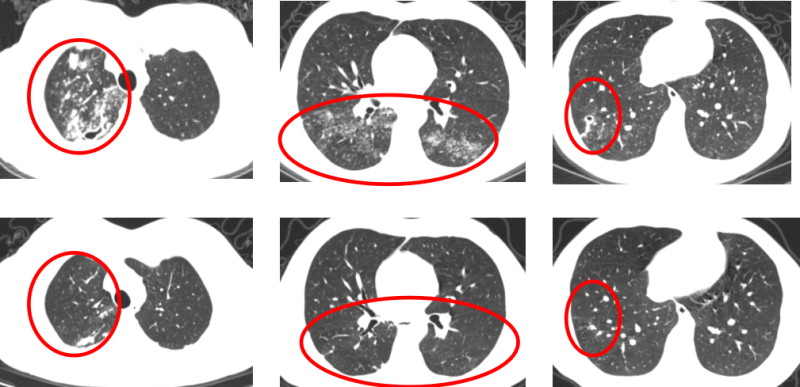

在治疗过程中,医护人员密切关注患者的病情变化和身体反应。经过6个月的规范治疗,患者的病情得到明显改善,复查结果显示,肺内病灶明显吸收,空洞已闭合,痰菌转阴,无咳嗽,身体状况逐渐恢复,顺利停药观察。